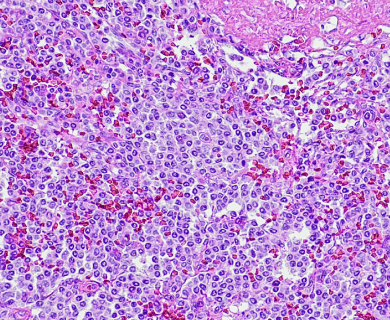

While epithelioid is a subtype of mesothelioma, there are further subtypes of the epithelioid type. Pathologists can identify these cell subtypes with immunohistochemistry.

Epithelioid mesothelioma has a better prognosis than other subtypes, but some epithelioid cell subtypes also have better prognoses than others. For example, adenomatoid cells are associated with a better mesothelioma survival rate.

Small Cell

Small cell mesothelioma doesn’t show the patterns found in small cell lung cancer. Those patterns include stream, ribbon or rosette. This cell type occurs with greater frequency in the abdomen. The survival rate is around 8 months.

Solid

Well-differentiated solid cells group in nests, cords or sheets. They resemble noncancerous abnormal cell growth. Poorly differentiated cells may look like large cell carcinoma or lymphoma.